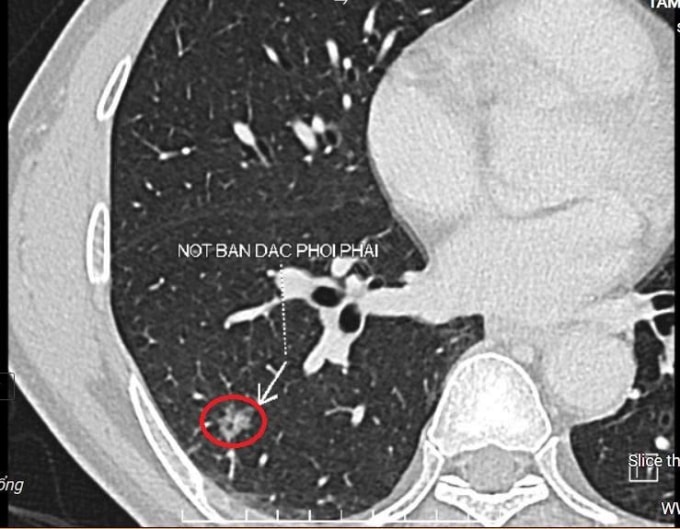

BS.CKII Lê Văn Thành, Trung tâm Chẩn đoán hình ảnh và Điện quang can thiệp, đánh giá nốt bán đặc kích thước 8x10 mm ở thùy dưới phổi phải của ông Hoàng thuộc nhóm Lung-RADS 4X, nhóm tổn thương có nguy cơ ác tính cao, cần xử trí sớm. Nhu mô phổi hai bên còn có một số nốt kính mờ và nốt đặc thuộc nhóm Lung-RADS 2, nguy cơ ác tính thấp, cần theo dõi thêm. Ông Hoàng hút thuốc lá hơn 40 năm, không có triệu chứng bất thường.

Nốt bán đặc ở thùy dưới phổi phải của ông Hoàng trên phim chụp cắt lớp vi tính. Ảnh: Bệnh viện Đa khoa Tâm Anh